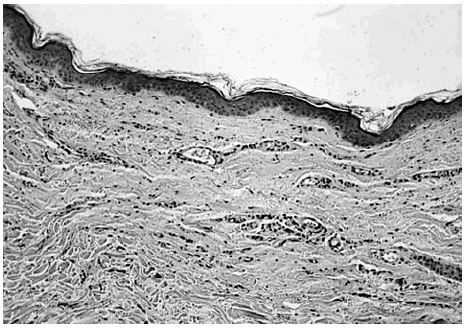

El estudio histopatológico evidenció únicamente una discreta atrofia epidérmica y un engrosamiento de las fibras colágenas en la dermis reticular en una de las biopsias (paciente 1) (fig. 3). En ninguna muestra histológica se evidenció elastosis actínica.

Fig. 3.--Mínima atrofia epidérmica. Engrosamiento de las fibras de colágena en la dermis reticular (H-E, ×40).